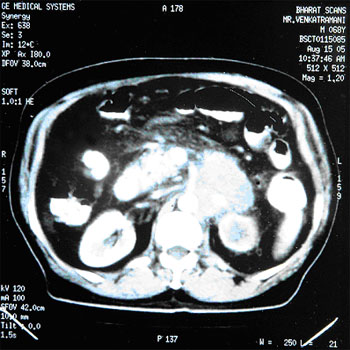

CA.Pancreas :

INITIAL STAGE

15-Aug-2005

AFTER HERBAL ONCOLOGY

21-Jan-2006